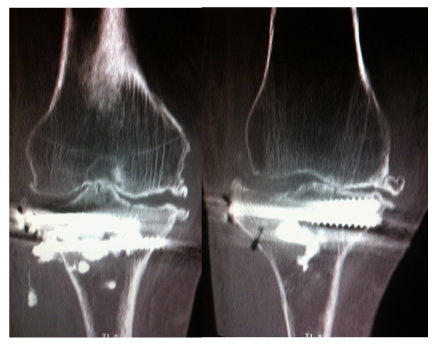

A 91-year-old woman sustained a right lateral tibial plateau depression fracture due to minor trauma (fall while walking). At presentation, the patient had significant knee effusion and was unable to weight bear on the injured leg. Nevertheless, her initial X-rays did not reveal anything more than severe arthritis of her knee. The subsequent CT scan - ordered because of high clinical suspicion - revealed a depression fracture of her lateral tibial plateau without cleavage (Figure 1). Apart from the tibial fracture, the patient had significant comorbidities including six fractured ribs, haemothorax and mild pneumothorax resulting from the same injury as well as cardiac arrhythmia (treated with a pacemaker), severe osteoporosis and adhesive intestinal obstruction. In order to achieve early mobilization of the patient and minimal knee stiffness, surgical treatment was chosen using a minimally invasive technique: Reduction of the depressed tibial plateau using balloon tibioplasty and stabilization of the fracture with hydroxyapatite cement and cannulated screws.

Figure 1 Clinical presentation, X-ray and CT scan.